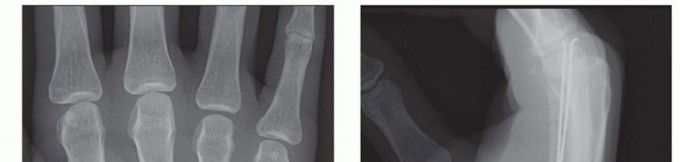

TECH FIG 1 • A. Retrograde (collateral recess) pinning. B,C. Angled distal metacarpal fracture. (continued)

TECH FIG 1 • (continued) D,E. Fracture stabilized with two pins that have been advanced to the base of the metacarpal. (Copyright Thomas R. Hunt III, MD, DSc.)